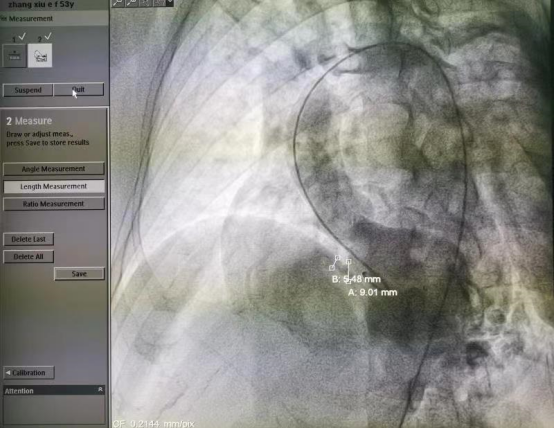

△术中通过数字血管造影机精确测量室间隔缺损大小